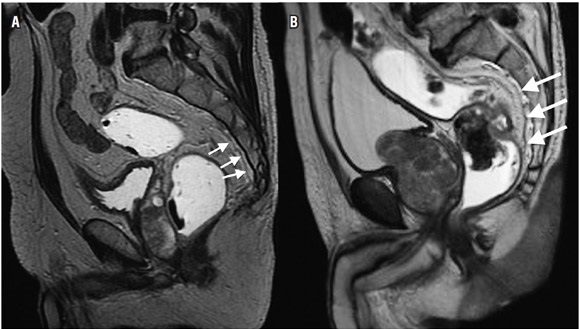

La estadificación del tumor depende directamente de su relación con la capa muscular propia y de la invasión con los órganos adyacentes (8). Un tumor T1 es aquel que se encuentra confinado a la mucosa, un tumor T2 es el que se extiende hasta la muscular propia (figura 3), un tumor T3 invade y se extiende más allá de la muscular propia (T3 temprano menor de 5 mm o T3 avanzado mayor de 5 mm) (figuras 4 y 5) y un tumor T4 es aquel que invade los órganos pélvicos (figura 6) (15). Los vasos pélvicos, la fascia parietal pélvica y la fascia mesorrectal no son considerados órganos (8).

El 80% de los tumores rectales son lesiones en estadio tumoral T3, siendo este un grupo heterogéneo de lesiones que presentan sobrevidas variables dependiendo de la extensión de la invasión más allá de la muscular propia (15). Los estadios T3 que tienen invasión menor de 5 mm tienen una sobrevida similar a los estadios tumorales T2, razón por la cual pueden ser agrupados para fines pronósticos y terapéuticos (15).

Para evitar errores debidos al volumen parcial, las imágenes deben ser obtenidas en un plano perpendicular a la capa muscular (8), reconociendo la capa muscular propia como una estructura hipointensa (negra), delgada, que rodea el recto (8). Dentro de los signos que sugieren una extensión más allá de la muscular propia (T3 avanzado) (figura 5) se encuentra la ulceración tumoral, un tumor que ocupe más de la mitad de la circunferencia, un tumor con un mayor compromiso longitudinal, metástasis ganglionares o a distancia (8).